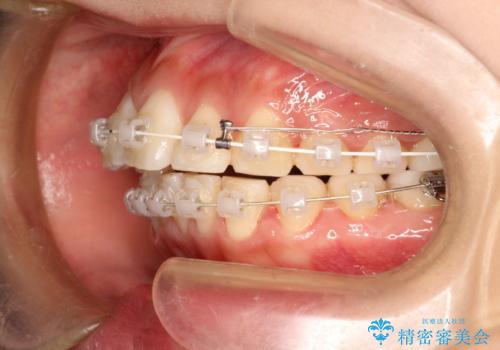

- 矯正装置

- 審美装置

- 治療期間

- 2年2ヶ月